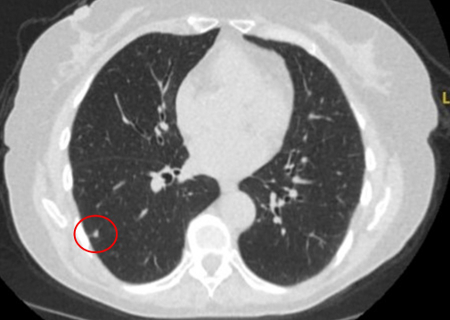

Benign nodules tend to have well-defined borders, while malignant nodules tend to be irregular or elongated. However, often a degree of overlap occurs and, taken alone, this feature cannot be reliably used as a discriminating factor.[Figure caption and citation for the preceding image starts]: Computed tomography (CT) showing a small left upper lobe nodule with smooth margins, subsequently found to be a solitary colorectal metastasis on resectionFrom the collection of Dr George Tsaknis, MD, PhD, FRCP(London), MRQA, MAcadMEd, PGCert; used with permission [Citation ends].